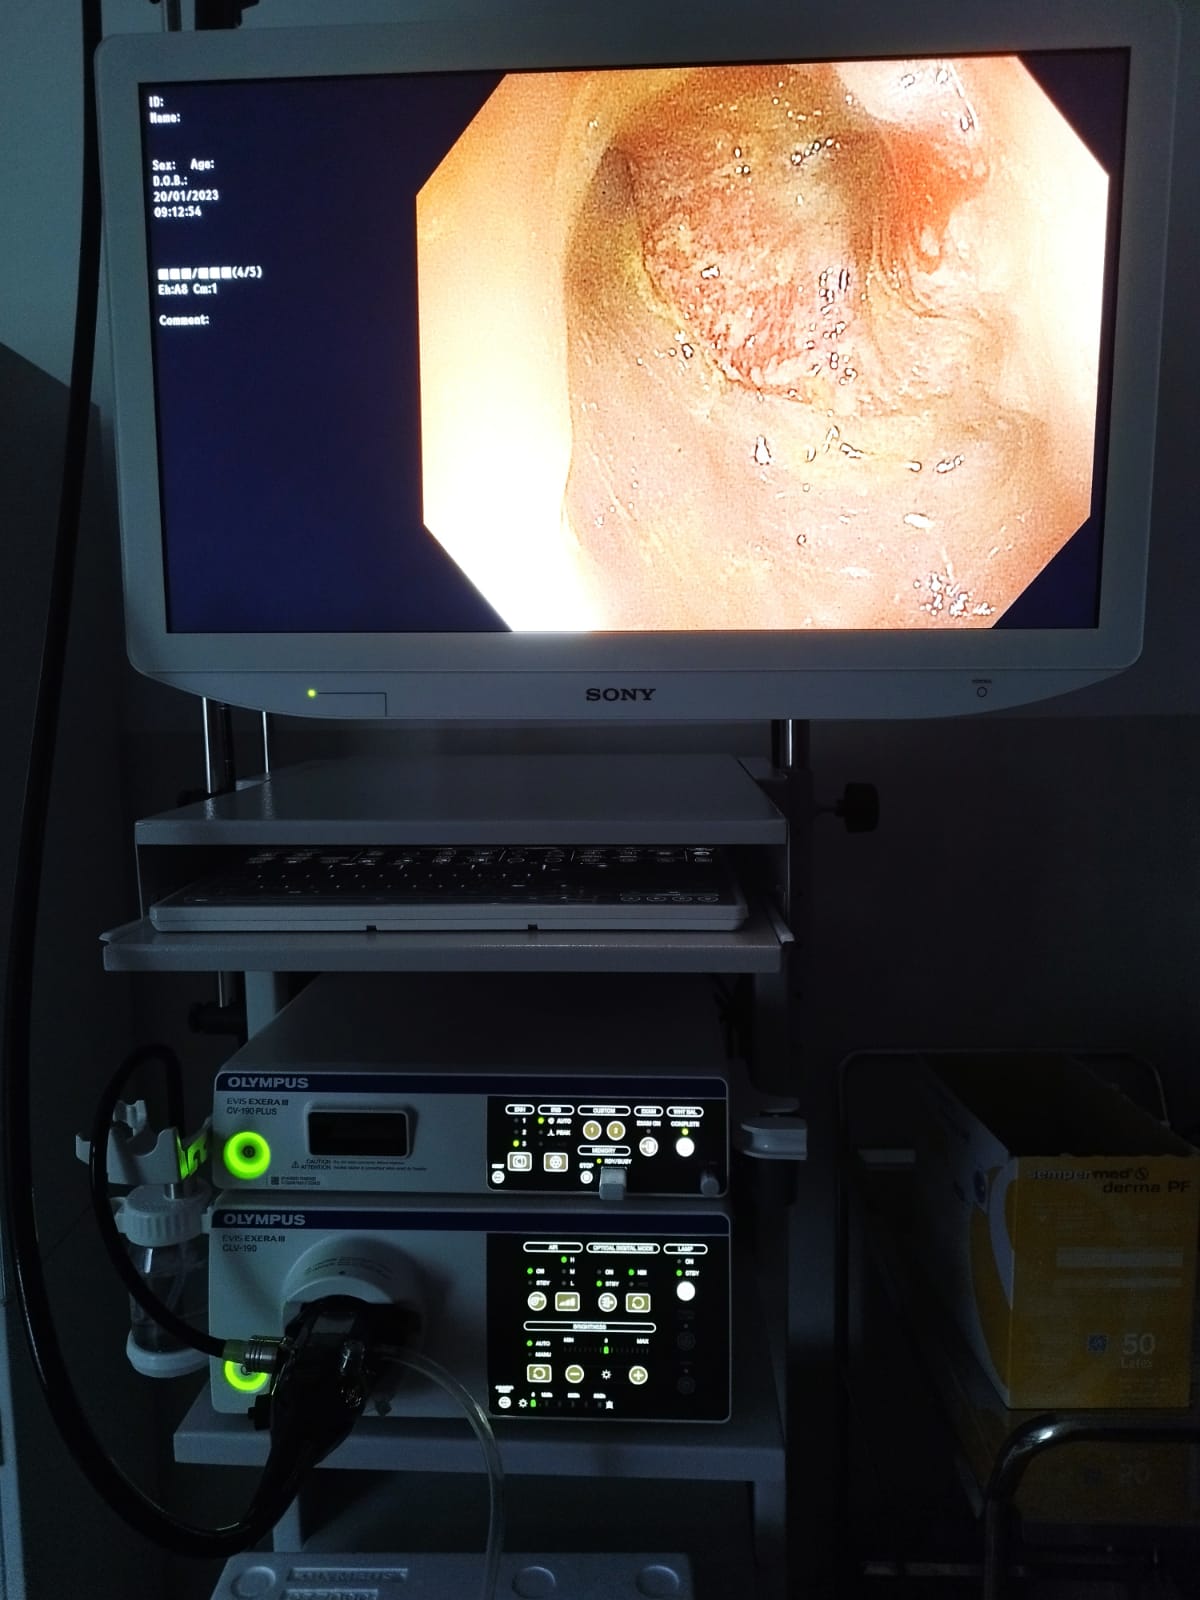

La finalul anului trecut, Consiliul Județean Gorj a finalizat procedura de achiziție iar recent a încheiat etapa de punere în funcțiune și dare în folosință a noului sistem de endoscopie digestivă superioară și inferioară de ultimă generație, care facilitează vizualizarea și examinarea detaliată, fiind compus din:

Noul echipament medical permite investigarea endoscopică cu bandă îngustă de culoare, care are rolul de a evidenția capilarele și structurile de pe suprafața mucoasei, ceea ce duce la o mai bună delimitare a leziunilor de la nivelul mucoasei.

„O afecțiune depistată la timp este mai ușor de tratat, iar prognosticul pentru pacient este mult mai bun. Este un aparat ultraperformant, mai ales datorită tehnicii NBI-narrow band imaging. Superioritatea aparatului se datorează tocmai tehnicii NBI, ceea ce îl diferențiază de alte aparate existente. Este creat un contrast sporit între vasele de sânge din mucoasa digestivă și țesuturile adiacente. Această tehnică ajută în depistarea precoce a tumorilor digestive și a altor leziuni inflamatorii din peretele digestiv. Acest fel de aparat există în clinicile și spitalele universitare din țară. De noul sistem endoscopic beneficiază atât pacienții internați în Secția Gastroenterologie, cât și ceilalți pacienți ai Spitalului Județean de Urgență Târgu Jiu, pe internare continuă, sau internare de zi”, a menționat dr. Roxana Gheorghițoiu, medic specialist gastroenterologie din cadrul Spitalului Județean de Urgență Târgu-Jiu.